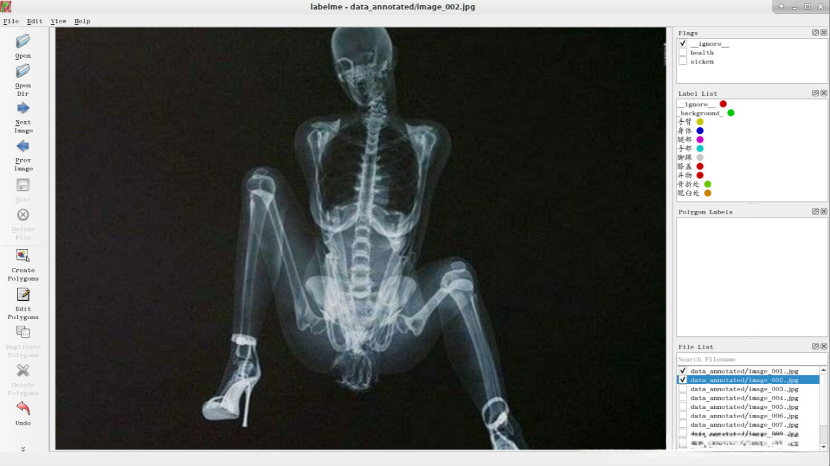

10.点击“Next Image”,将图像中人是否是健康的,无法判定时选择“ignore ”。

将图像中人体标注出来并选择相应的label。